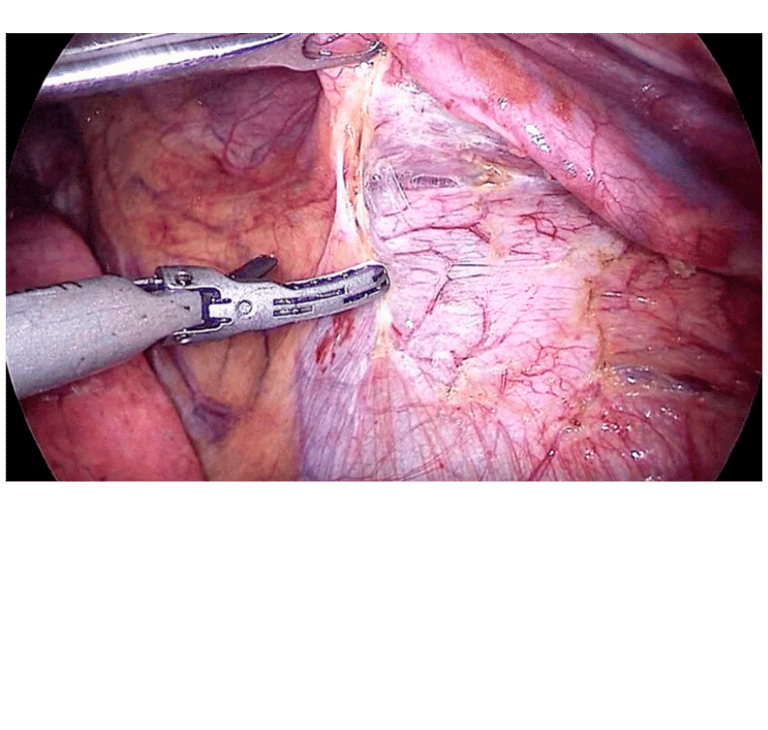

Terapia Híbrida percutanea, endovascular y quirúrgica

Terapia multidisciplinaria, individualizamos al paciente, para otorgar el angioacceso que mejor se ajuste a sus características.

Manejo quirúrgico para angioaccesos definitivos

Nos especializamos en la colocación de accesos vasculares intra auriculares por cirugía de mínima invasión videasistida y creación de neo conductos con injertos sintéticos